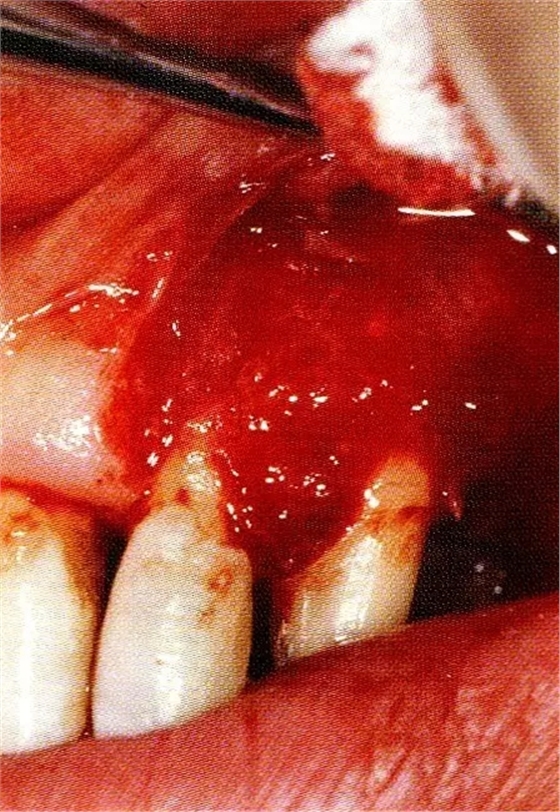

案例3針對(duì)3壁性垂直性骨缺損使用非吸收性膜進(jìn)行再生治療,再翻瓣時(shí)進(jìn)行骨形態(tài)修整的病例。

▲圖7-1左下6近中可觀察到3壁性垂直性骨缺損。此病例考慮到齦瓣供血關(guān)系,在前磨牙部位進(jìn)行了減張切開,沒有進(jìn)行縱切開。并利用刮治器、牙周外科用車針進(jìn)行了徹底的骨缺損部位搔刮。